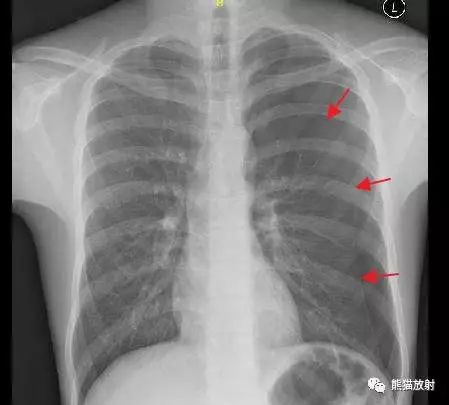

胸部x线片示左侧心尖少量气胸,邻近胸膜粘连.

右侧气胸(肺被压缩约70%) ↓:气带宽度略大于患侧胸廓的1/2,右肺明显

胸 片 正常 左侧胸腔积液 右侧气胸

图15 仰卧位胸片显示深沟征,提示气胸